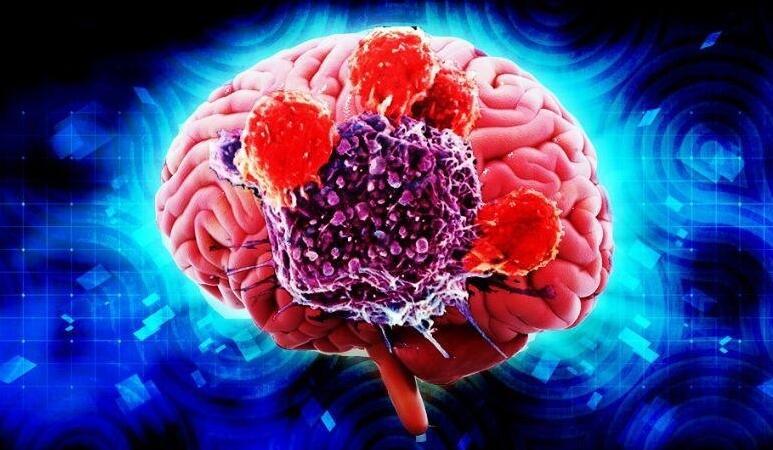

脑癌也是很痛苦的癌症之一,首先脑癌会出现头痛,部分脑癌患者病发时会出现撞墙的情况就是因为疼痛。

并且脑癌因为病发于大脑是会引起精神失常,甚至在晚期是会出现脑疝的,很多患者收到的折磨都觉得生不如死。